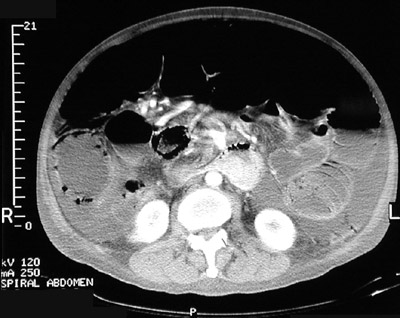

| The abdominal CT scan views above and below demonstrate the uncommon condition known as pneumatosis intestinalis in which small collections of air (seen here as black spaces) appear in the bowel wall. These scan also reveal a large amount of ascitic fluid as well as free air in the abdomen. |